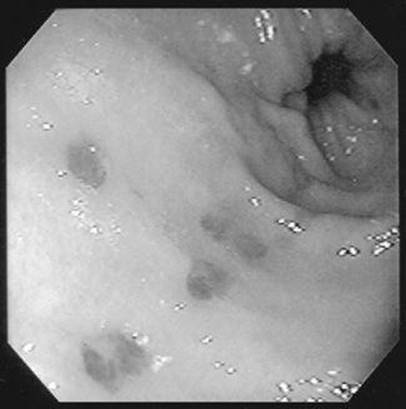

A 37-year-old man with a history of alcohol abuse is transferred to your hospital with a history of hematemesis and melena the day before. He has numerous spider telangiectasias on his upper body and mild asterixis. What lesion is being demonstrated on upper endoscopy?

Figure 1-1

Esophageal varices in the distal esophagus that have undergone band ligation.